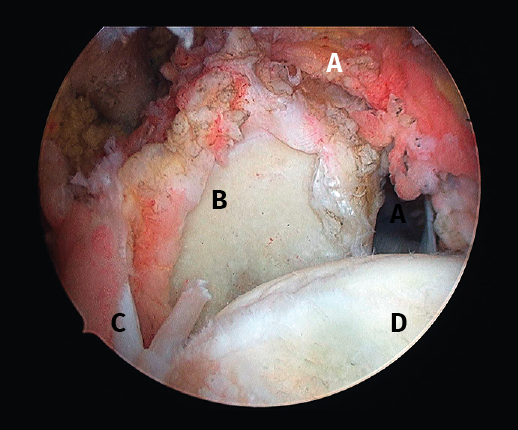

Figura 4. Rotura de supra- e infraespinoso en forma de L invertida con presencia de 2 capas. A: tendón supraespinoso; B: tendón infraespinoso; C: cabeza humeral.

Figura 5. Rotura de tipo C1. A: rotura pequeña de espesor completo del supraespinoso; B: cabeza humeral.

Sin embargo, las clasificaciones basadas en el tamaño de la rotura deben ser bidimensionales, ya que la visión unidimensional puede ser engañosa, al mostrar el tamaño de la rotura solo desde el plano anteroposterior(4). Por esta razón, proponemos el sistema de clasificación del manguito posterosuperior sugerida por Snyder, que aporta información no solo del tamaño, sino del número de tendones afectados y la presencia de tejido cicatricial(7). En las lesiones de tipo C1 la lesión atraviesa todo el espesor del tendón y en el eje transversal es pequeña y punzante (Figura 5). Las de tipo C2 son roturas de espesor completo pero la distancia entre los extremos de la rotura es menor de 2 cm con escasa retracción (Figura 6). En las de tipo C3 la rotura afecta en sentido transversal entre 3 y 4 cm con mayor retracción implicando 2 tendones (Figura 7). Y las de tipo C4 son la rotura masiva del manguito de los rotadores con una afectación de espesor completo de toda la anchura de 2 o más tendones asociando importante retracción (Figura 8).

Figura 8. Rotura de tipo C4. A: rotura masiva del tendón supraespinoso con presencia de degeneración grasa; B: glena; C: rotura masiva del tendón infraespinoso; D: cabeza humeral.